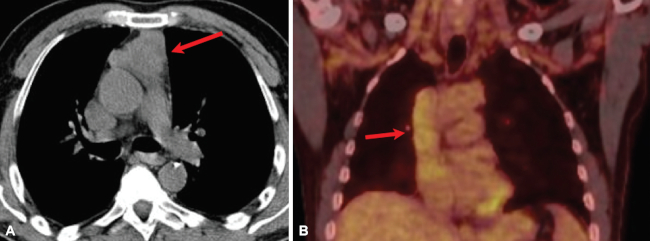

En timomas, la imagen en TC generalmente evidencia una masa homogénea de partes blandas con bordes bien delimitados y una morfología lobulada, redonda u ovalada. En ocasiones, se pueden ver calcificaciones o componentes de baja densidad que representan necrosis (especialmente en tumores grandes) (►Fig. 5).16 Hasta el 5% de los timomas invasivos pueden tener metástasis al momento de presentación y el PET-CT, siendo un método de evaluación de todo el cuerpo, es de utilidad para detectarlas.17

La capacidad de 18F-FDG PET-CT para diferenciar los timomas invasivos (alto riesgo) y no invasivos (bajo riesgo) suscita controversias, pues se observa una marcada superposición en la captación de timomas no invasivos e invasivos. Sin embargo, existe un relativo consenso en que los timomas invasivos presentan mayor captación en comparación con los no-invasivos.18